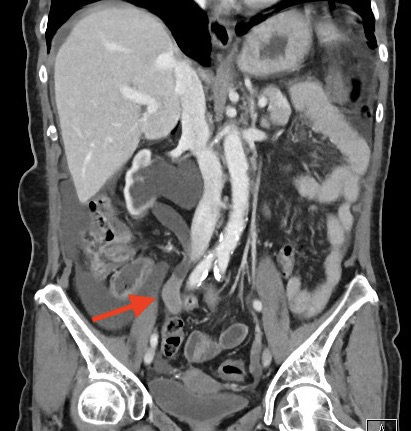

La urografía por tomografía computarizada (TC) – Uro TAC en nuestro país – es actualmente la técnica de imagen más precisa para el diagnóstico del CVUA, siendo de esta manera considerada como el estándar (Figuras 1 y 2)20. La TC puede ayudar además a predecir la etapa T del tumor primario (precisión hasta del 88%), siendo útil en la detección de metástasis regionales y a distancia (para esto último debe incluirse siempre una TC de Tórax)21. Sin embargo, presenta deficiencias en la detección de lesiones planas y tumores <3mm (hasta 40% de sensibilidad), casos en los cuales habitualmente es necesaria una evaluación endoscópica complementaria22. La TC con emisión de positrones (PET) constituye una alternativa promisoria para la evaluación de metástasis a distancia, con una sensibilidad superior a la TC convencional en estudios iniciales (85 vs. 50%), sin embargo requiere más validación para recomendar su uso rutinario en el estudio del CVUA23. Puede ser considerada en pacientes con función renal alterada que impida utilización de medio de contraste yodado.

Fig. 2. Imagen axial de TC con CVUA en uréter derecho